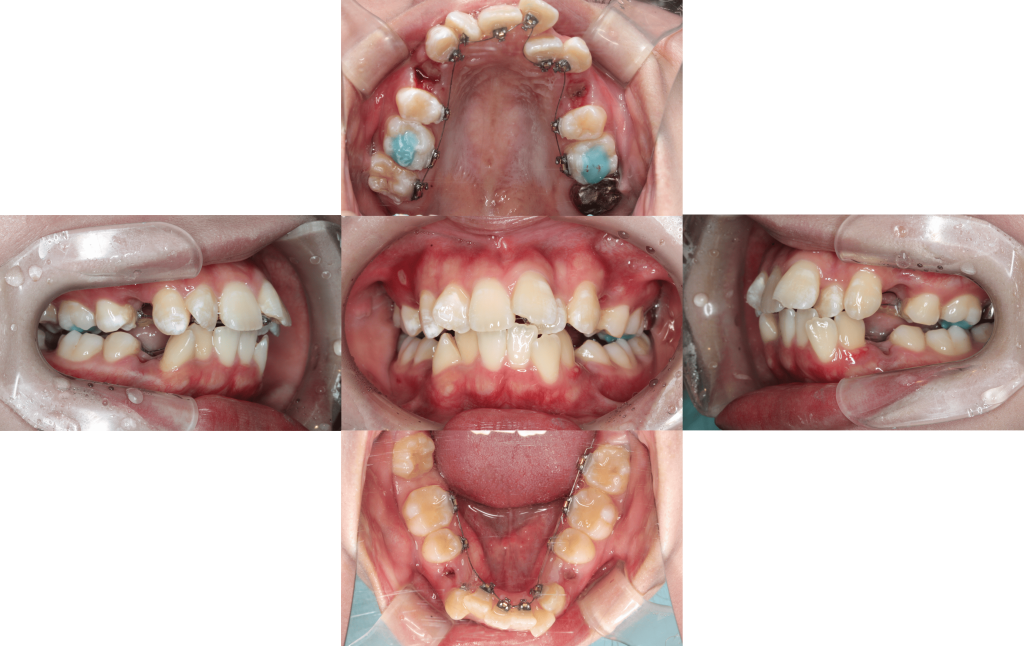

Before

After

初診

装置装着

約6か月後

約1年後

約1年6か月後

約2年後

約2年6か月後

約3年後

年齢層

20代

性別

女性

主訴

・1┴1でっぱり・凸凹な歯並び・Eライン・上下のかみ合わせ

治療費用

¥1,320,000

治療期間

約3年(治療中)

抜歯

上下顎両側第一小臼歯

矯正の装置

マルチブラケット装置(裏側矯正)

副作用、リスク

歯肉退縮,歯根吸収,疼痛,咬合の違和感,装置の違和感,虫歯,歯肉炎